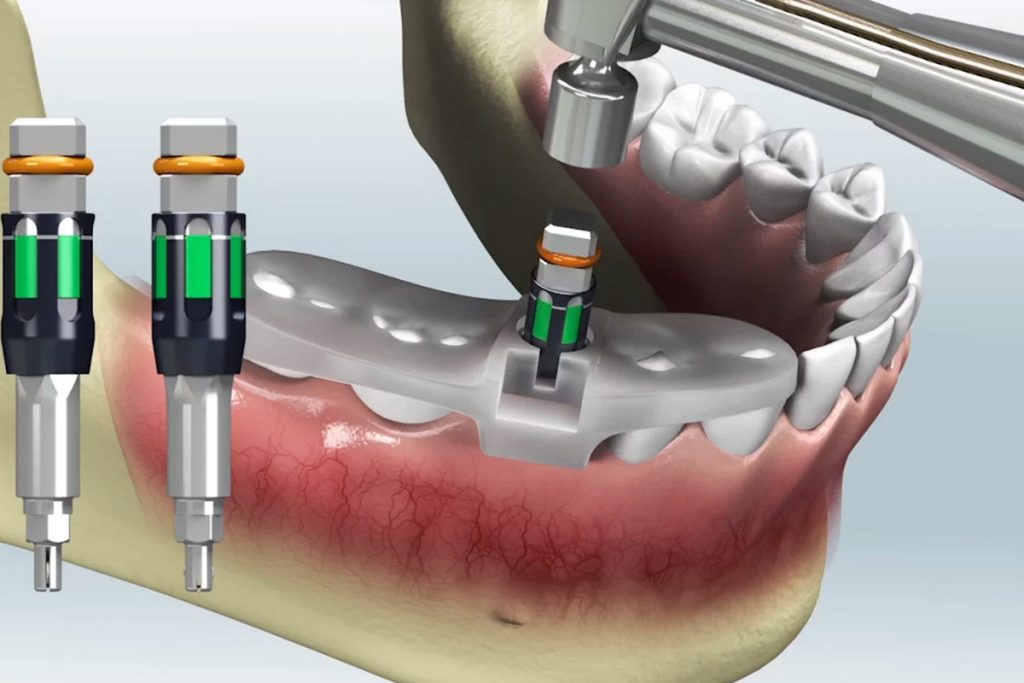

۵. ساخت گاید جراحی سهبعدی

براساس طرح نهایی، یک گاید جراحی با پرینتر سهبعدی ساخته میشود. این گاید روی لثه یا دندانهای باقیمانده بیمار قرار میگیرد و به جراح کمک میکند زاویه، عمق و محل دقیق دریلکاری را بدون انحراف انجام دهد.

۶. انتخاب کیت جراحی مناسب

برای همخوانی کامل با گاید، از کیتهای مخصوص مانند Y-T یا MegaGen استفاده میشود. این ابزارها تضمین میکنند که دریلها دقیقاً مطابق طراحی دیجیتال عمل کنند و خطر خطا یا شکست درمان کاهش یابد.

۷. جراحی با هدایت دیجیتال

در روز جراحی، گاید در دهان بیمار قرار میگیرد و اگر تراکم استخوان مناسب باشد، جراحی بدون برش لثه (فلپلس) انجام میشود. در این حالت، سوراخهایی دقیق روی لثه ایجاد و ایمپلنت با کمترین آسیب وارد استخوان میشود.

۸. کارگذاری ایمپلنت با دقت میلیمتری

ایمپلنت دقیقاً در همان محل، زاویه و عمقی قرار میگیرد که در طراحی مشخص شده است. اگر همه مراحل با دقت انجام شوند، نتیجه نهایی بسیار نزدیک به طرح دیجیتال خواهد بود و خطاهای معمول در روش سنتی به حداقل میرسد.